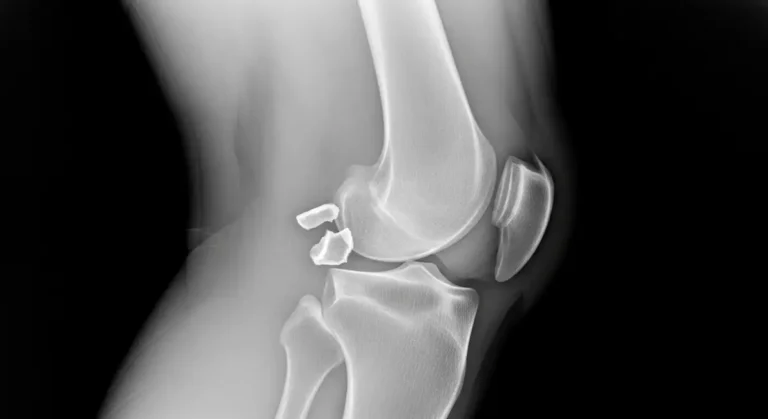

A síndrome de Osgood-Schlatter é uma dor irritativa no ponto em que o tendão patelar se ancora na tuberosidade da tíbia. Saltos, corridas e chutes aumentam a tração do quadríceps e inflamam essa área de crescimento. É comum em crianças…